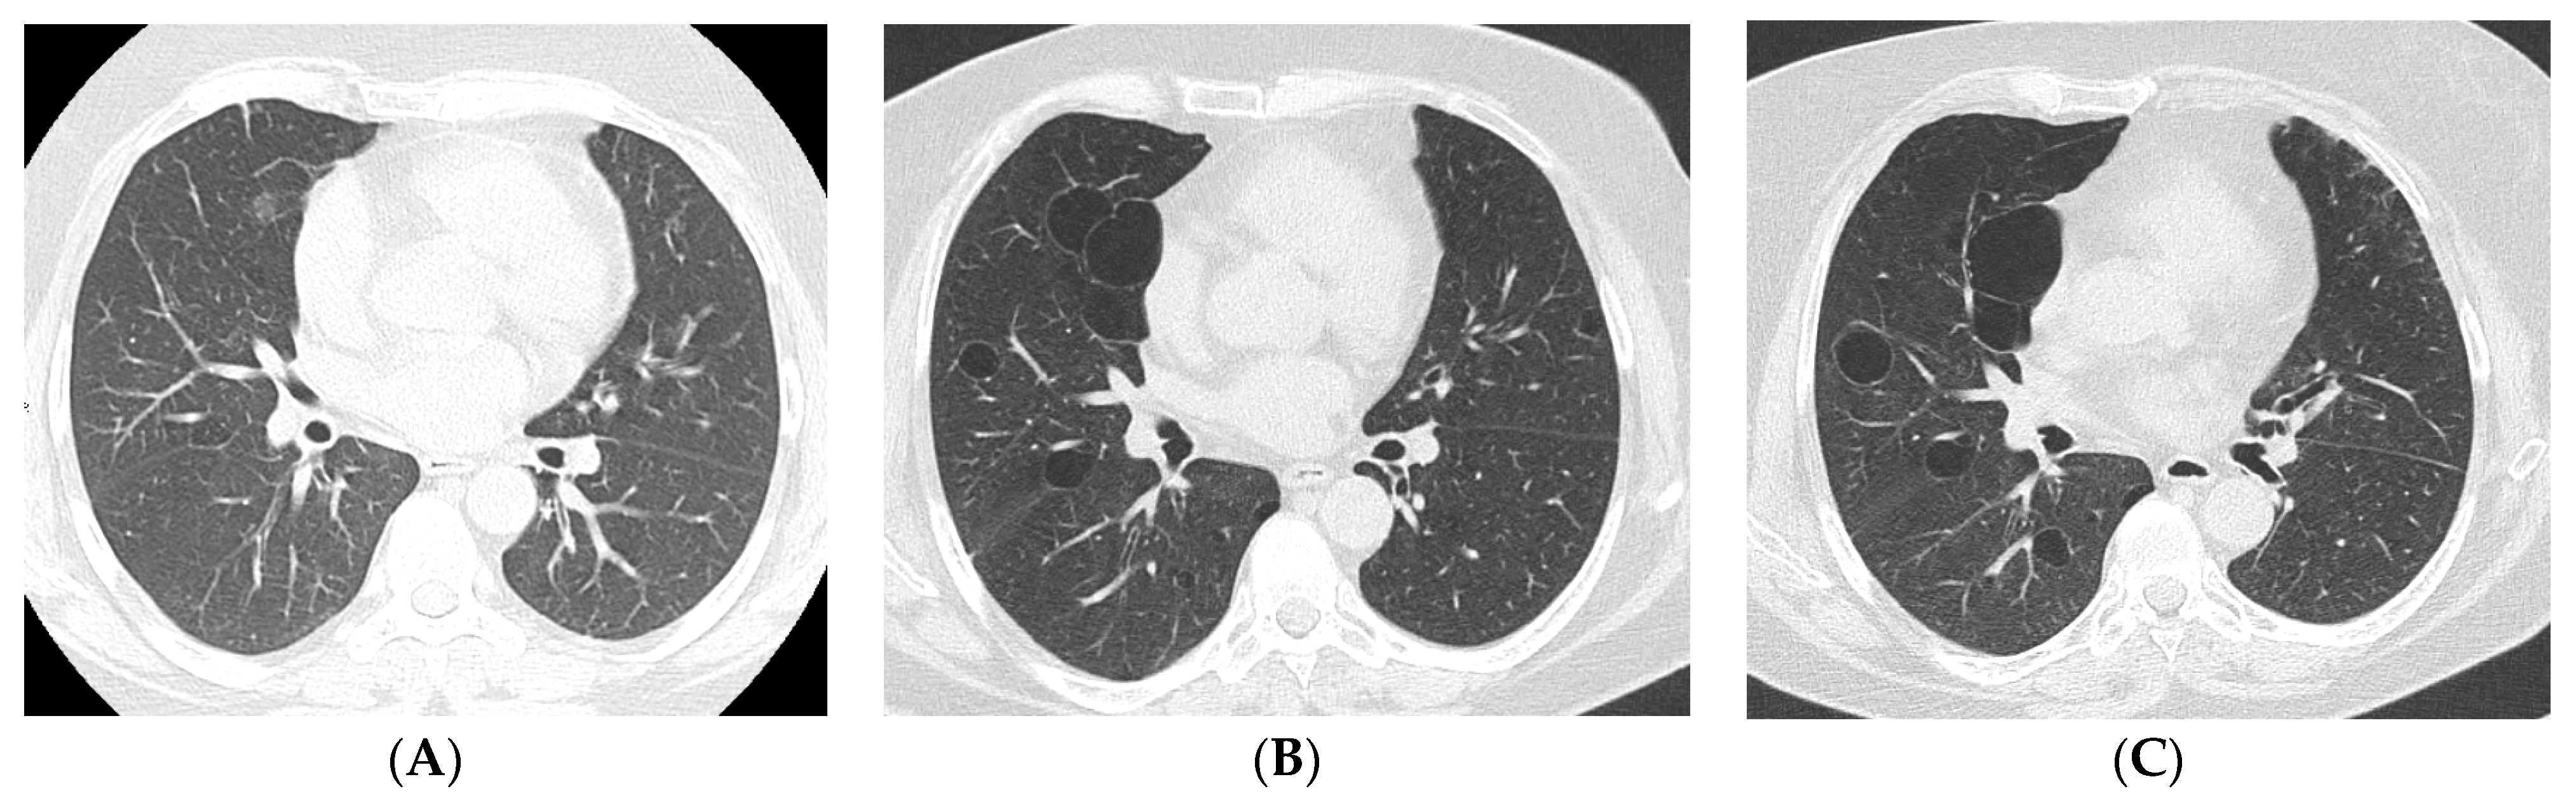

4. Imaging and Histopathology of ILD in pSS

4.1. How Does Radiologic/Histopathologic Pattern Influence the Clinical Picture and Management of pSS-ILD Patients? What Is the Role of Lung Biopsy?

- Dong, X.; Gao, Y.-L.; Lu, Y.; Zheng, Y. Characteristics of primary Sjögren’s syndrome related lymphocytic interstitial pneumonia. Clin. Rheumatol. 2021, 40, 601–612. [Google Scholar] [CrossRef] [PubMed]

- Ito, I.; Nagai, S.; Kitaichi, M.; Nicholson, A.G.; Johkoh, T.; Noma, S.; Kim, D.S.; Handa, T.; Izumi, T.; Mishima, M. Pulmonary manifestations of primary Sjogren’s syndrome: A clinical, radiologic, and pathologic study. Am. J. Respir. Crit. Care Med. 2005, 171, 632–638. [Google Scholar] [CrossRef]

- Enomoto, Y.; Takemura, T.; Hagiwara, E.; Iwasawa, T.; Okudela, K.; Yanagawa, N.; Baba, T.; Sakai, F.; Fukuda, Y.; Nagaoka, S.; et al. Features of usual interstitial pneumonia in patients with primary Sjögren’s syndrome compared with idiopathic pulmonary fibrosis. Respir. Investig. 2014, 52, 227–235. [Google Scholar] [CrossRef] [PubMed]